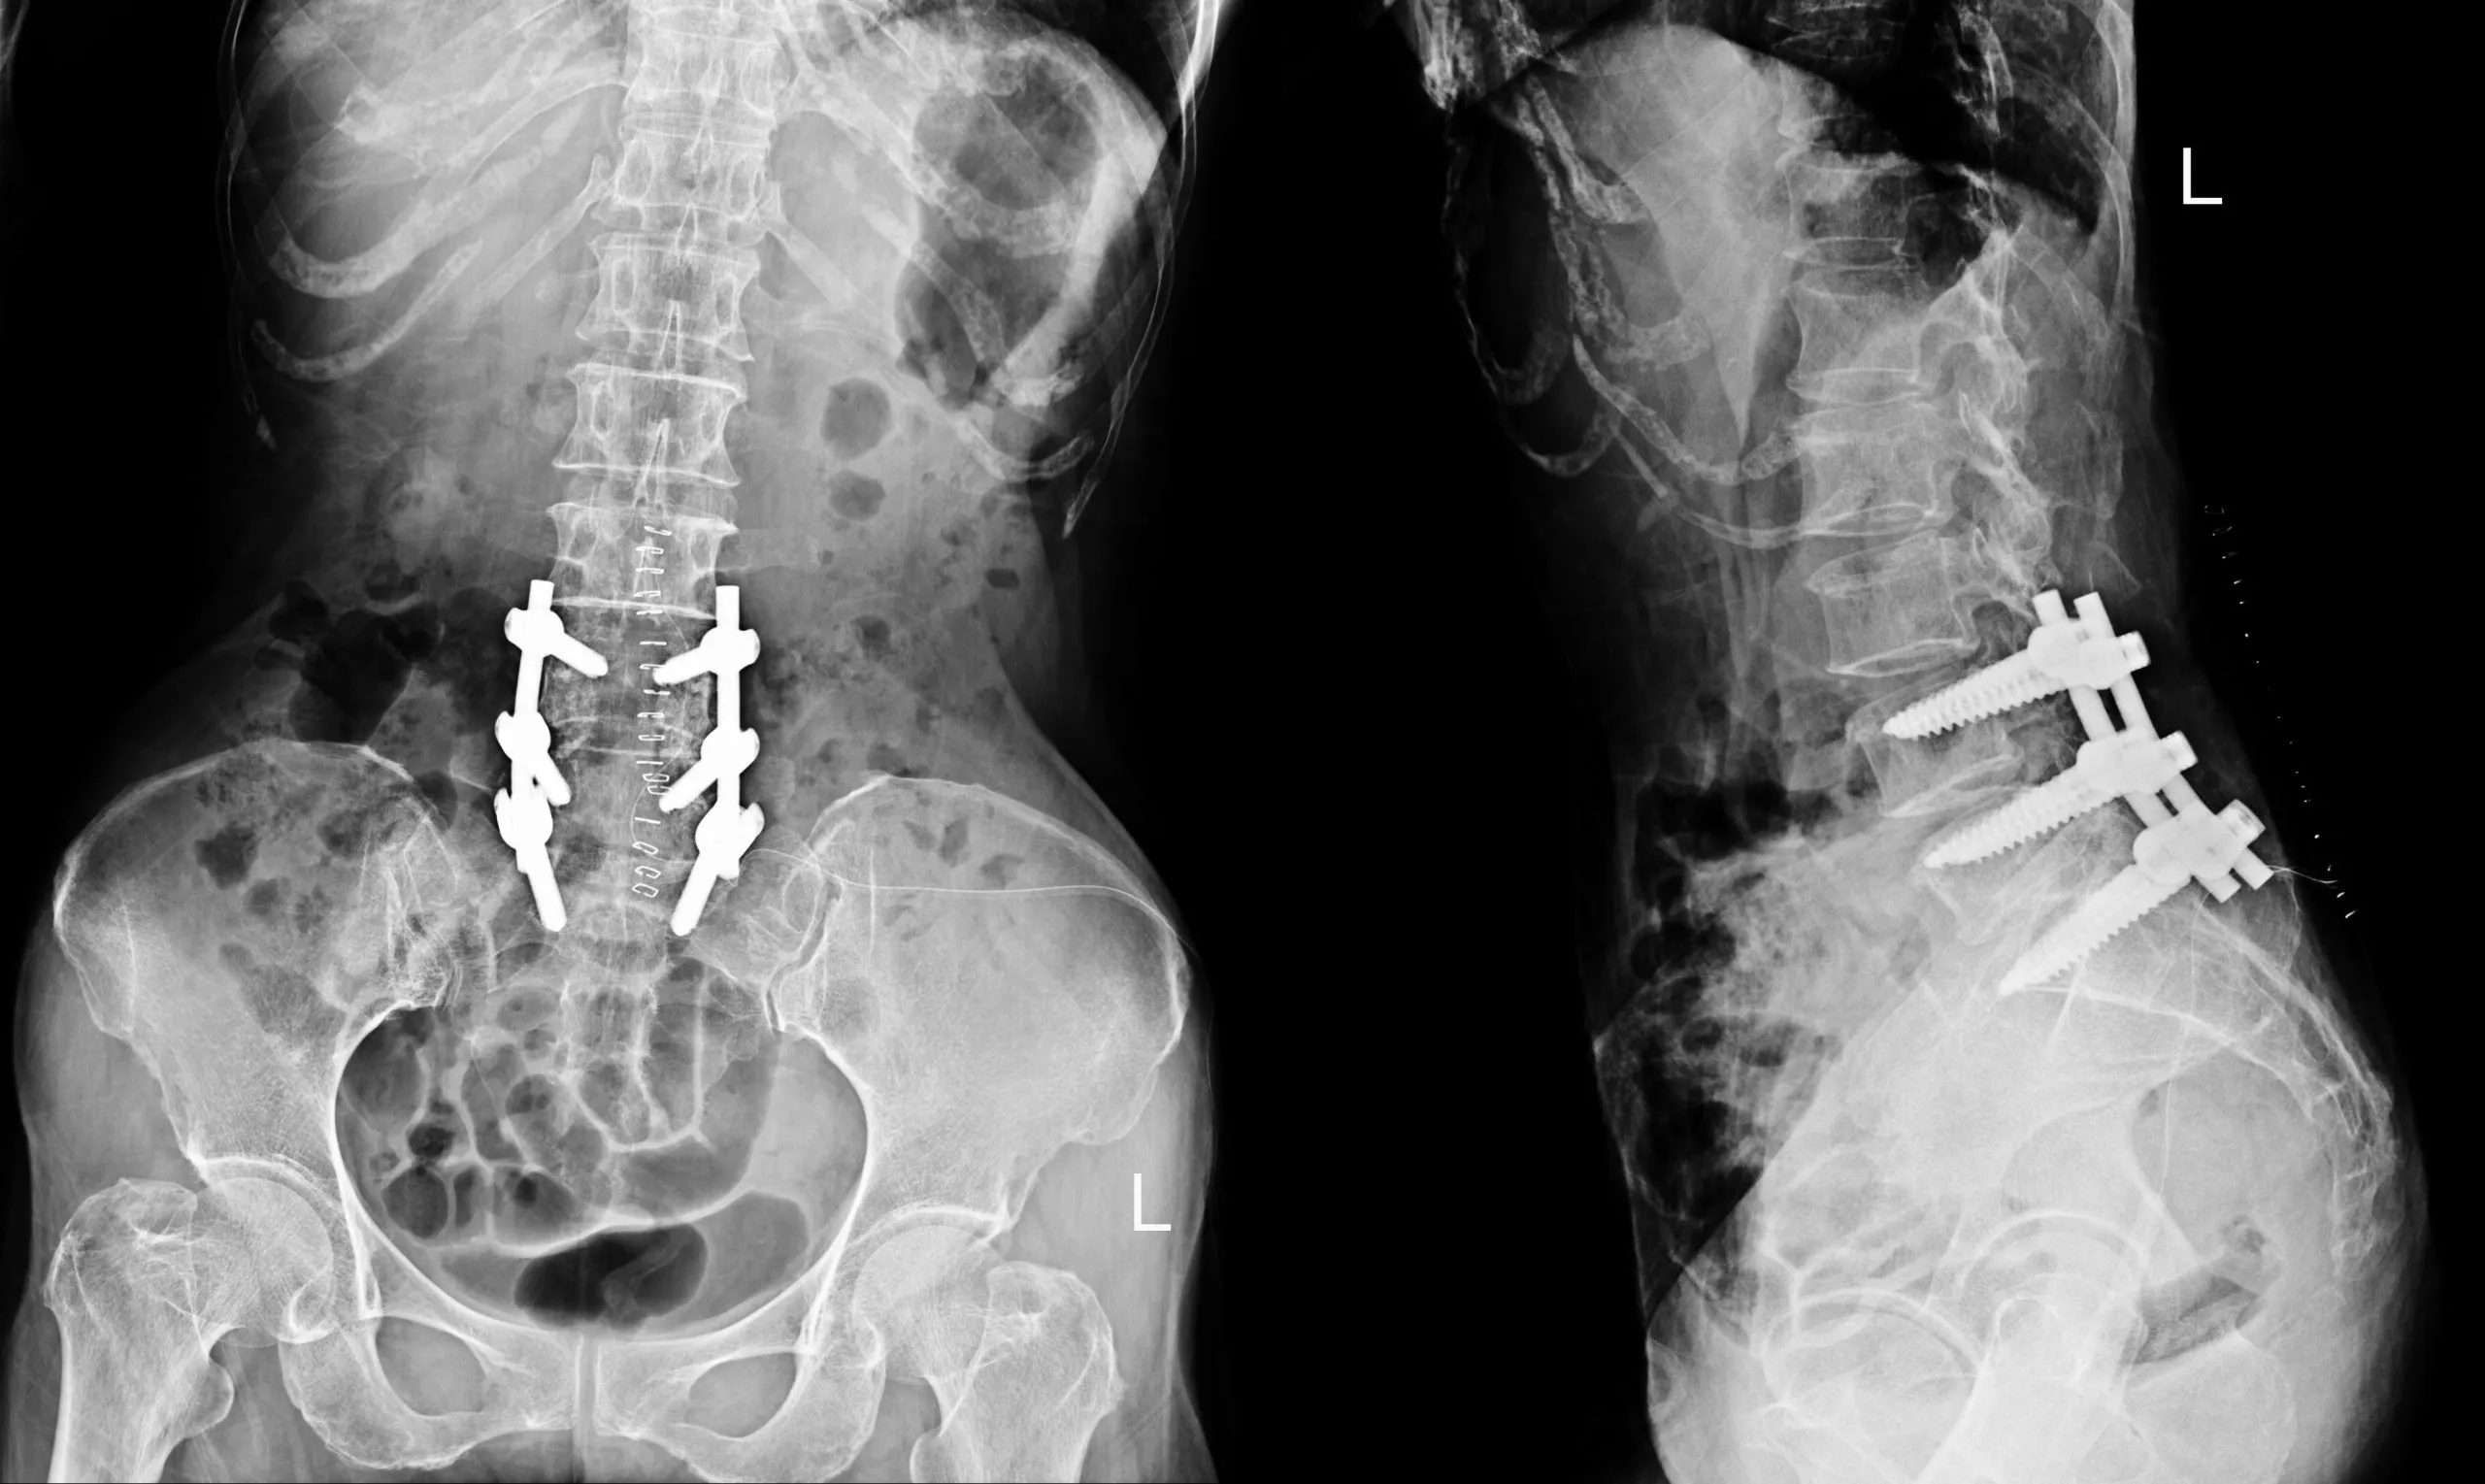

The main goal of TLIF is to remove a damaged intervertebral disc—the cushion between the vertebrae—and replace it with a bone graft and a structural spacer, usually a cage made of titanium or a high-performance polymer like PEEK. This graft and cage restore the correct height between the vertebrae and help the fusion process. Over time, the bone graft grows and fuses the adjacent vertebrae into a single, solid bone, eliminating movement at that segment. To provide immediate stability while the fusion matures, the surgeon also installs hardware, such as pedicle screws and rods.

- Pedicle Screw Fixation: To provide rigid stabilization, the surgeon places pedicle screws into the vertebrae above and below the fused level. These screws are then connected with rods, creating a solid internal construct that holds the vertebrae in place while the bone fuses.

Hardware Failure or Malposition: The screws and rods provide the initial stability for the fusion. Hardware can break, loosen, or be misplaced. Screw malposition can irritate nerves or compromise the stability of the construct. Hardware failure may require revision surgery..